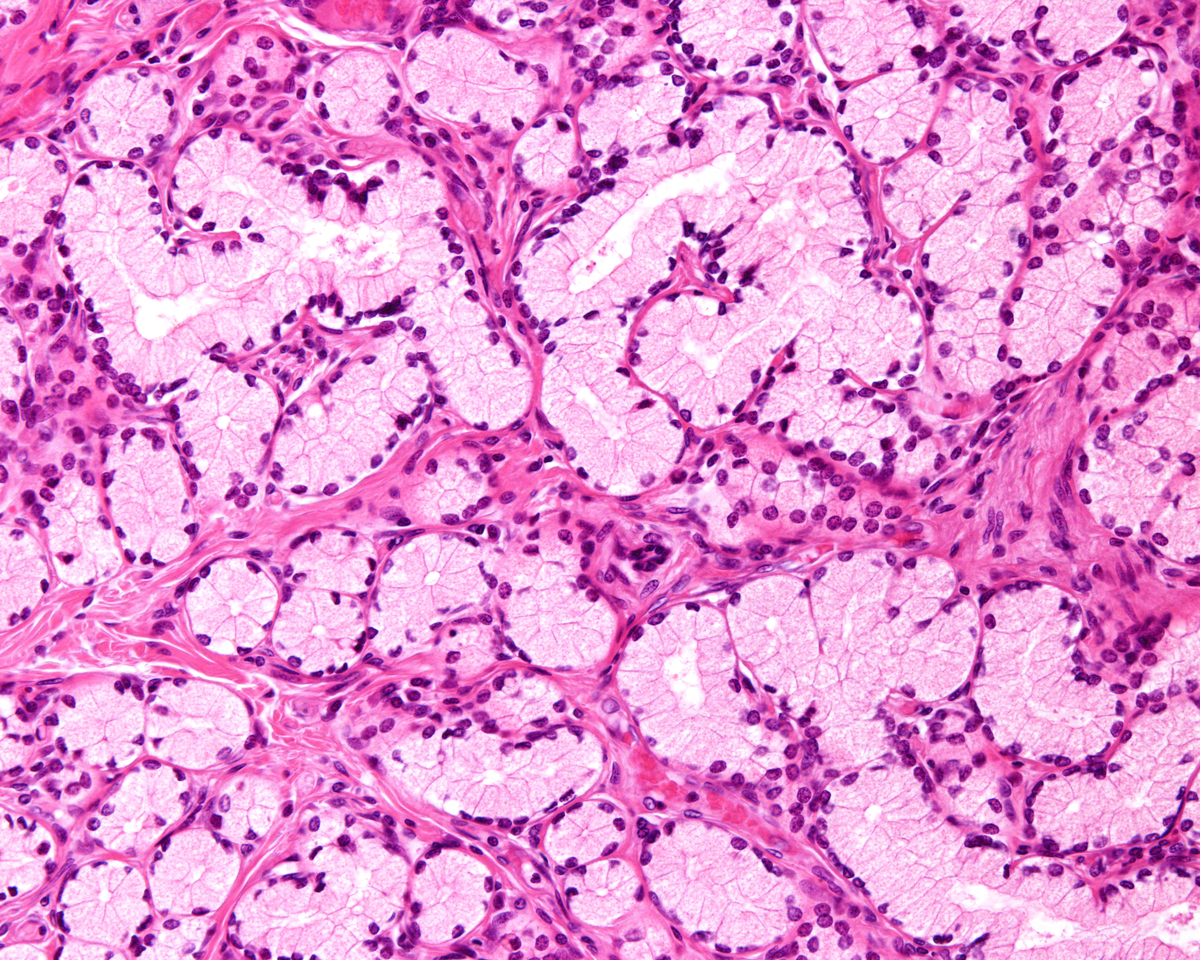

根据实验结果,可以得出以下结论:肝细胞癌细胞与正常肝细胞在形态和生长特征上存在明显差异,肝细胞癌细胞呈现出不规则、多形性及大量核分裂现象等特点,而正常肝细胞呈现出规则、单形性及较少核分裂现象等特点。此外,肝细胞癌细胞在免疫组化染色中常呈现出AFP、CD133等肝细胞癌标志物的阳性表达,而正常肝细胞则不表达或表达较少。因此,肝细胞癌细胞与正常肝细胞可以通过形态学特征、生长特征及免疫组化标记等方面进行有效区分。

肝细胞癌细胞与正常肝细胞的鉴别方法